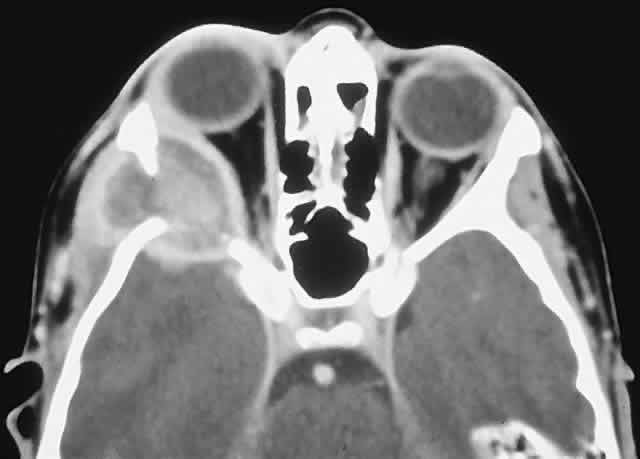

IMAGING. ABCs occurring in long bones have a characteristic uni- or multilocular expansile appearance. However, the radiology in the orbital bones is not specific and consists of destruction or expansion (Fig. 6). If expansile, the mass may have a thin cortical margin, but this is often absent as a consequence of erosion through to periorbita or dura. The central area is inhomogeneous, shows patchy enhancement, and can have multiple fluid levels, particularly in the more mature lesions.85,88 MRI may demonstrate recent hemorrhage in cases with an acute onset.

Fig. 6. An 11-year-old girl with a past history of acute lymphoid leukemia presented with decreasing left vision and proptosis. She had a left best corrected vision of 20/30, a relative afferent pupillary defect, and 2 mm of proptosis. A. CT demonstrated a destructive heterogeneous mass arising in the posterior ethmoid and sphenoid sinuses and involving the left orbital apex. A subtotal removal of the mass was achieved through a frontal craniotomy and orbitotomy. B. Histology showed a fibrous stroma containing giant cells, lymphocytes, and trabeculae of osteoid and bone (hematoxylin-eosin, × 20). There were also areas with giant cells, hemosiderin-laden macrophages, and small foci of aneurysmal sinusoids, leading to a diagnosis of solid aneurysmal bone cyst. There was no evidence of recurrence at follow-up 6 years later. C. Histology from another patient with aneurysmal bone cyst shows a typical cavernous, blood-filled space lacking endothelial lining, pericytes, or smooth muscle (hematoxylin-eosin, × 20). (A from Rootman J: Diseases of the Orbit: A Multidisciplinary Approach, p 373. Philadelphia: JB Lippincott, 1988.)